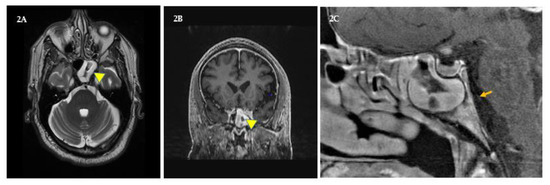

Figure 2.

Sphenoid sinusitis. (A and B) shows transaxial and coronal views of inflammation in the patient’s left sphenoid sinus (yellow triangles). (C) shows a sagittal view of his congested right sphenoid sinus and the plausible path of his right sixth cranial (abducens) nerve (orange arrow) along the pons. However, congestion in the right pons cranial nerve-VI (CN6) region was not seen, and increased intracranial pressure as cause of CN6 palsy was not ruled out.

In November 2018, the patient experienced sinus pain and intracranial pressure that did not abate with yoga, self-hypnosis, saline rinses, and naproxen. He experienced diplopia and orthostatic difficulties when fixating on vertical edges of walls to balance when standing-up, which to the patient felt like the two same vertical edges were side by side (binocular double vision). In addition, he had a slight convergent right eye squint, that is, his right eye was turning slightly inwards towards his nose. Furthermore, while driving, he saw phantom traffic lane lines obliquely cutting into his lane from the right. He stopped driving and managed diplopia with a right eye patch. Soon diplopia worsened, interfered with reading and daily functions; and by month’s end (December), he was prescribed a 10-diopter base out Fresnel lens prism over his right eye (by coauthor, A.L.) after his misalignment was measured by alternate cover testing with hand-held prisms [28]. In addition, his neuro-ophthalmologist advised that the patient’s diplopia might be due to right CN6 palsy, triggered by a sinus infection that might be causing his pain and intracranial pressure. Alternatively, given the patient’s medical history, it could be due to his chronic diabetes and/or MS, and that such palsies are almost always temporary. At New Years, as nasal lavage thickened, appeared dark, and became more painful, the patient was prescribed amoxicillin to reduce infection. By late January, he was symptom free [22,26,28,29]. In March 2019, sinus pain, pressure, and diplopia returned, and at that time he was undergoing his postradiation therapy follow-up. His transaxial and coronal MRIs in addition to his tumor’s status showed that his left sphenoid sinus was more inflamed than the right (Figure 2A and B, yellow triangles). Moreover, while MRIs showed no congestion and no legion(s) in the right pons CN6 region (Figure 2C, orange arrow), the effects of intracranial pressure on CN6 could not be ruled out. Since temporary diplopia is known to be due to ipsi- as well as contralateral CN6 palsies induced by sphenoid sinusitis and increased intracranial pressure, it was conjectured that his symptoms will subside as inflammation diminishes. Later that month, his pain and diplopia were resolved with saline rinses, naproxen, and yoga. CN3 (oculomotor nerve) palsy was ruled out because the patient’s right eyelid was not droopy (no ptosis), the right pupil was not dilated, and the eye was not shifted temporally. CN4 (trochlear nerve) palsy was ruled out because diplopia did not worsen when looking down. In addition, his March MRIs showed that his tumor was greatly reduced, his MS was stable, and he had no new CNS lesions or infarctions [22,23,24,25,26,27,28,29].